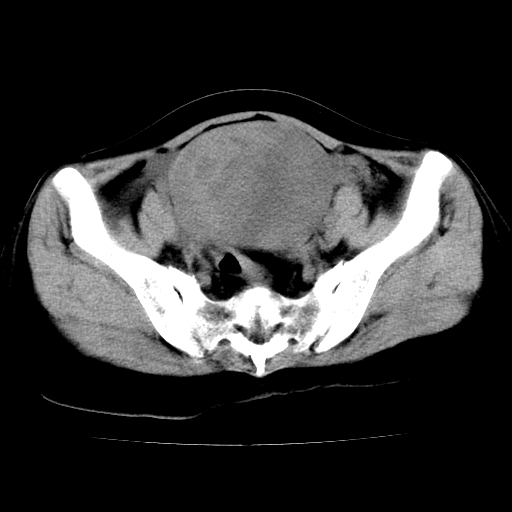

标题: CT24785:女,62岁,发现下腹部肿物半年。 [打印本页]

女,62岁,发现下腹部肿物半年,下腹部不适。

考虑回肠间质瘤,不排除卵巢癌可能。

该年龄性别首先考虑平滑肌肉瘤可能性大,其他待排除。